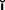

An accurate charting of the state of the dentition reveals important information about the condition of the teeth and facilitates treatment planning. Adequate charting (Fig. 1-19), in addition to all periodontal information, must show the presence or absence of teeth, dental caries, restorations, wear faceting and abrasions, fractures, malformations, and erosions. Missing teeth often have an effect on the position of adjacent teeth (see also the section on arch integrity in Chapter 3). Similarly, the presence of dental caries on one interproximal surface should alert the examiner to carefully inspect the adjacent proximal wall, even if caries is not apparent radiographically. The degree and extent of caries development over time can have a considerable effect on the eventual outcome of fixed prosthodontic treatment. The condition and type of the existing restorations are noted (e.g., amalgam, cast gold, composite resin, all-ceramic). Open contacts and areas where food impaction occurs must also be identified. The presence of wear facets is indicative of sliding contact sustained over time and thus may indicate parafunctional activity (see Chapter 4). Wear facets are often easier to see on diagnostic casts, however (see Chapter 2); during the clinical examination, the location of any observed facet is recorded. Fracture lines in teeth may necessitate fixed prosthodontic intervention, although minor hairline cracks in walls that are not subject to excessive loading can often go untreated and simply be observed at recall appointments (see Chapter 32). The location of fractures should be indicated on the chart, as should any other abnormalities.

Fig. 1-19 A, An appropriate charting system designates the location, type, and extent of existing restorations and the presence of any disease condition, all of which become part of the permanent patient record. B, Radiographic findings obtained from a full-mouth series are correlated with the clinical findings and noted in the record. C to E, Charting is performed to provide a quick reference to conditions in the mouth. The following may be useful: (1) Amalgam restorations (C) are depicted by an outline drawing blocked in solidly to show the size, shape, and location of the restoration. (2) Tooth-colored restorations (D) are depicted by an outline drawing of the size, shape, and location of the restoration. (3) Gold restorations (E) are depicted by an outline drawing inscribed with diagonal lines to show the size, shape, and location of the restoration. (4) Missing teeth are denoted by a large X on the facial, lingual, and occlusal diagrams of each tooth that is not visible clinically or on radiographs. (5) Caries is recorded by circling the tooth number located at the apex of the involved tooth and noting the presence and location of the cavity in the description column corresponding to the tooth number on the right. (6) Defective restorations are recorded by circling the tooth number and noting the defect in the description column.

(Modified from Roberson T, et al: The Art and Science of Operative Dentistry, 4th ed. St. Louis, Mosby, 2002.)